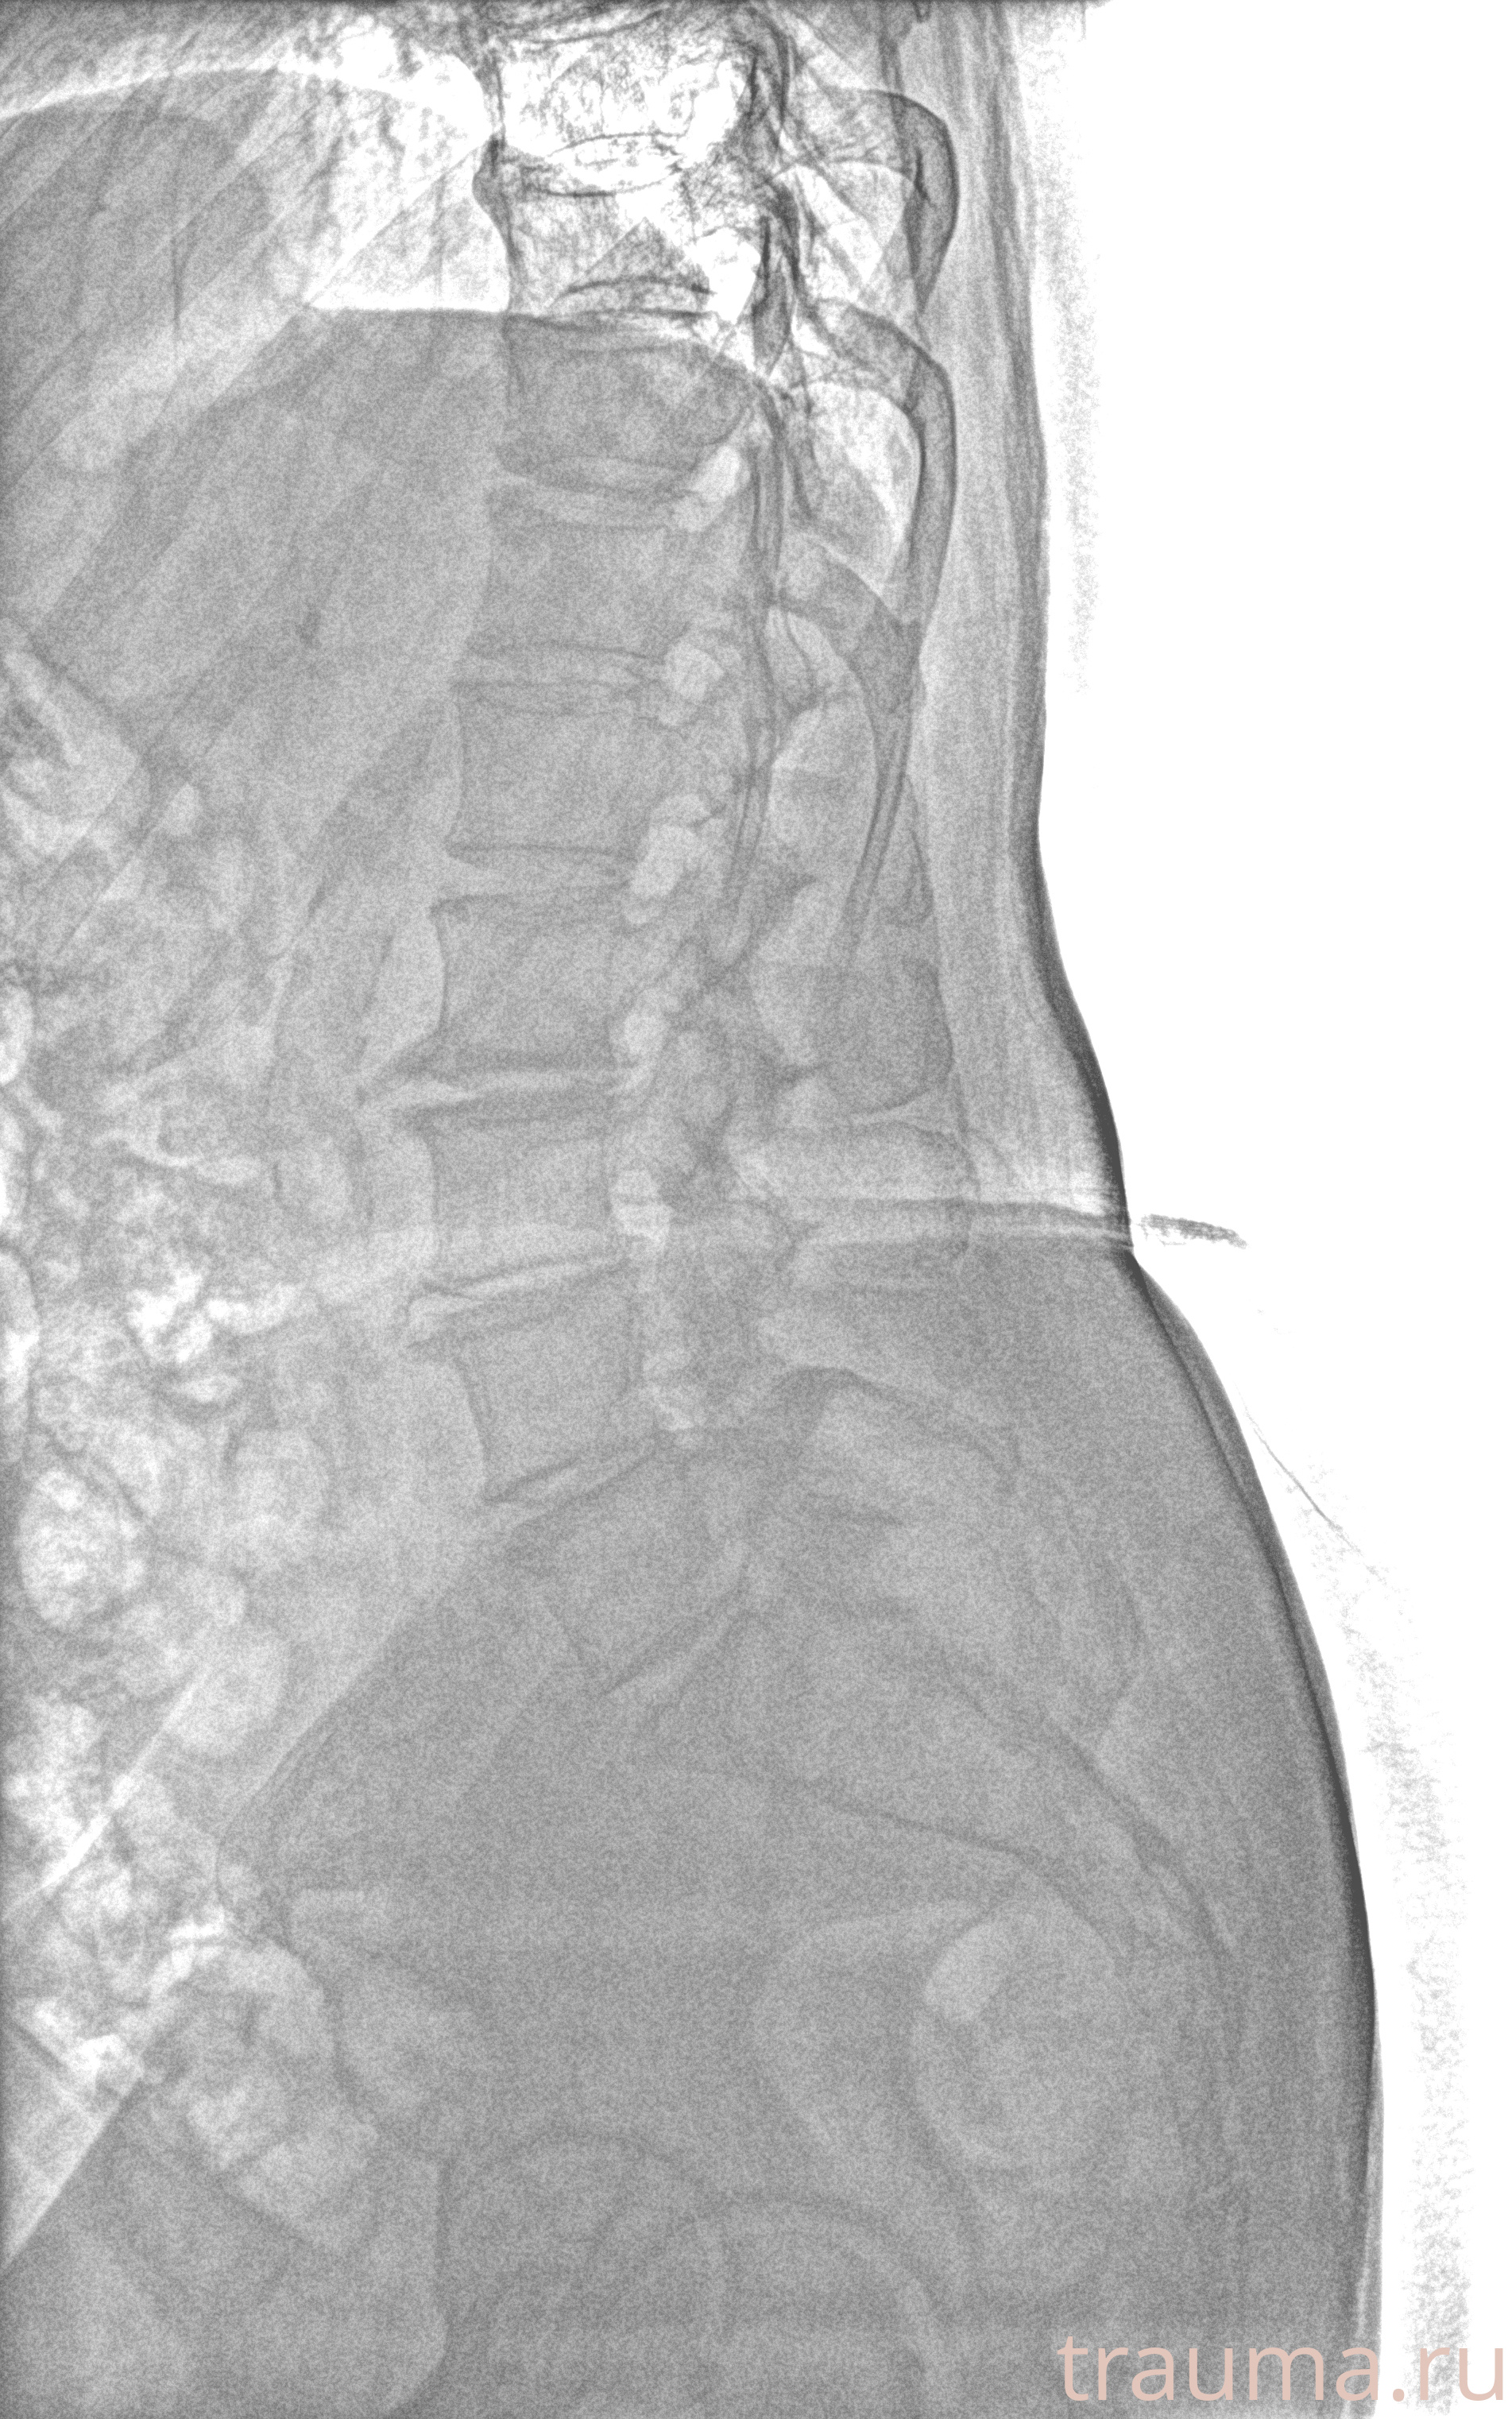

Рентгенограммы

Рентген на дому: по вашему адресу приезжает врач-рентгенолог, травматолог-ортопед с мобильным рентгеновским аппаратом, проводит диагностику травмы или заболевания, делает необходимые рентгенограммы, дает рекомендации по дальнейшему лечению. Получить качественные снимки в домашних условиях возможно благодаря уникальной методике, разработанной МосРентген Центром для института  Склифосовского